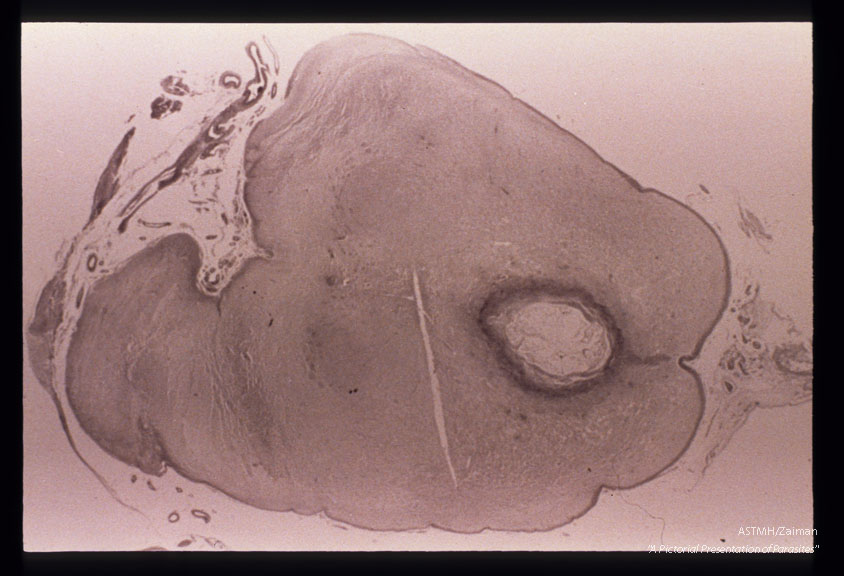

Encephalitis. Pons with necrosis around aqueduct which is obstructed leading to periventricular necrosis in the ventricular system anterior to it.

Toxoplasma gondii

Description: Encephalitis. Pons with necrosis around aqueduct which is obstructed leading to periventricular necrosis in the ventricular system anterior to it.